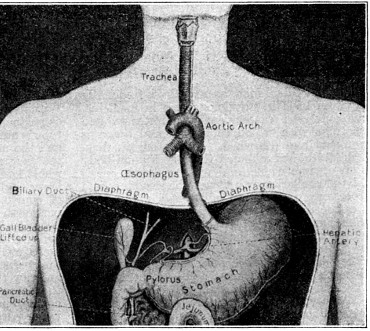

ITS STRUCTURE—ORGANIZATION INTO SYSTEMS—FUNCTIONS—SPECIAL SENSES—NERVOUS SYSTEM—PERSONAL HYGIENE—PREVENTION OF DISEASE—INTERDEPENDENCE OF BODY AND MIND—EUGENICS—ILLUSTRATIONS AND CHARTS.